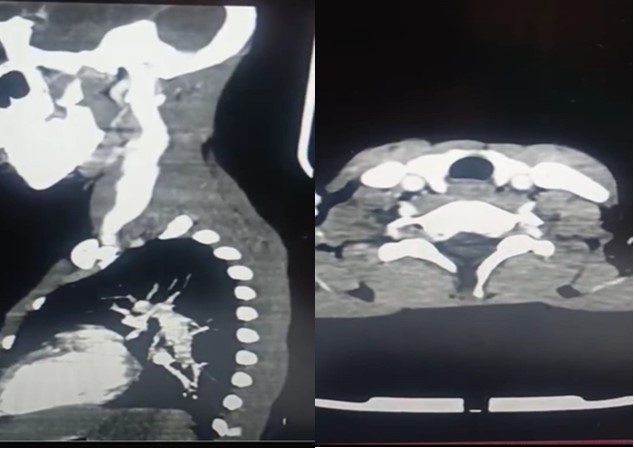

Ultrasonography (USG) of the neck showed fusiform dilatation of the lower segment of the IJV with a caliber of 4cm increasing to 7cm on Valsalva maneuver. In a previous USG imaging 3 years ago, it was about 2cm and 4 cm consecutively. Contrast-enhanced computed tomography (CT) of his neck and mediastinum excluded any mediastinal mass or anomaly and confirmed the previously known dilatation of the left internal jugular vein without thrombosis (Figure 2).

Figure 2.(c Left,d Right) (c) sagittal CT-image shows well-defined (d) axial CT-image showing dilated left IJV with homogenous huge left IJV

(c Left,d Right) (c) sagittal CT-image shows well-defined (d) axial CT-image showing dilated left IJV with homogenous huge left IJV